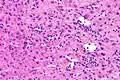

The primary characteristic of MASLD is the accumulation of lipids in the liver, largely in the form of triglycerides.[19] However, the mechanisms by which triglycerides accumulate and the reasons that accumulation can lead to liver dysfunction are complex and incompletely understood.[19][47][48] MASLD can include steatosis along with varied signs of liver injury: either lobular or portal inflammation (a form of liver injury) or ballooning degeneration. Similarly, NASH can include histological features such as portal inflammation, polymorphonuclear cell infiltrates, Mallory bodies, apoptotic bodies, clear vacuolated nuclei, microvesicular steatosis, megamitochondria, and perisinusoidal fibrosis.[16] Hepatocyte death via apoptosis or necroptosis is increased in MASH compared with simple steatosis, and inflammation is a hallmark of MASH.[32]

NASH (inflammation) and fibrosis stage 2 Lobular inflammation

Lobular inflammation

NAFLD comprises two histological categories: NAFL, and the more aggressive form NASH. The presence of at least 5% fatty liver is common to both NAFL and NASH, but the features of substantial lobular inflammation and hepatocyte injuries such as ballooning or Mallory hyaline only occur in NASH. The majority of NAFL cases show minimal or no inflammation.[3][5][7] Pericentral and perisinusoidal fibrosis occur more often in adult-onset NASH, whereas portal fibrosis is more common in children with the disorder. NASH represents a more advanced stage of NAFL and is associated with poor outcomes such as cardiovascular events, cirrhosis, or hepatocellular carcinoma. ICD-11 does not use the term NAFL as it was deemed confusing with the family of disorders NAFLD. The preferred descriptions are instead: MAFLD without NASH or simple steatosis and "NASH". Also, the modifier with or without fibrosis or cirrhosis completes the diagnostic description.[3][7]